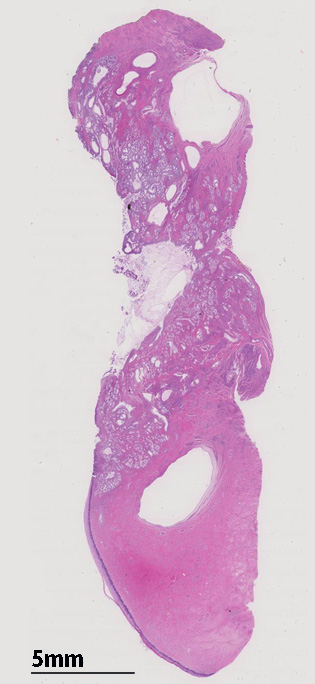

case: 46歳女性 水様性帯下があり受診。画像で子宮頸部嚢胞多発を指摘されconizationとなる。

頸管壁の1/2以内に限局することが多いが, 約40%の症例では頸部腫大や粘液様ないし水様帯下増加をきたしCT, MRIで頸部の多発嚢胞形成として認められる。臨床的に悪性腺腫adenoma malignumとの鑑別が大きな問題となる